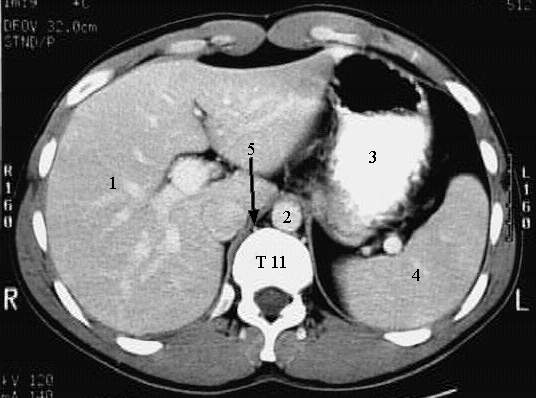

Radiology Images

Abdomen - Cross 1

1. Liver.

2. Abdominal Aorta.

3. Stomach.

4. Spleen.

5. Azygos vein.